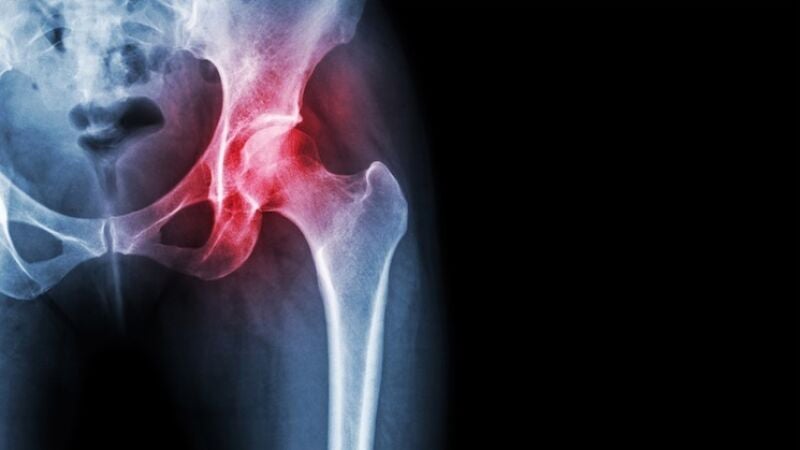

Aproximadamente uno de cada seis pacientes mayores de 70 años ha sufrido alguna fractura de fragilidad y, de ellos, más de un tercio sufrirá nuevas fracturas. La fractura de cadera es la que mayor mortalidad, dependencia y gasto sanitario conlleva, con solo uno de cada cuatro pacientes recuperando la autonomía previa a la fractura.